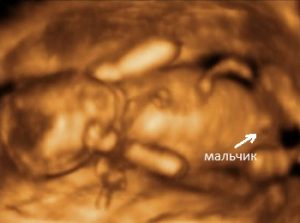

2. 3D-ультразвук

Имейте в виду, что даже УЗИ не является на 100% точным, и были случаи, когда люди покупали одежду для мальчиков, а потом оказывалось, что у них девочка и наоборот.

Самый достоверный способ узнать пол ребенка – это 3D или 4D УЗИ на сроке 25-30 недель.